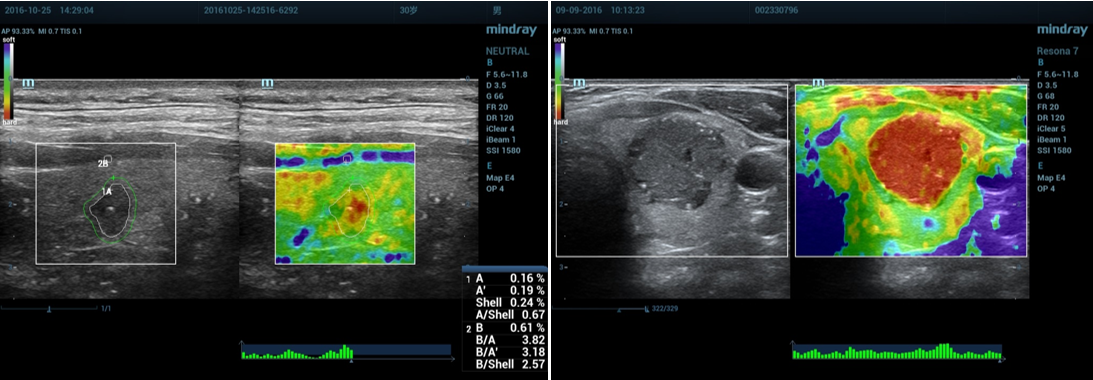

3、数据测量:

①按Measure,选择测量应变比(描记法)。

②分别描记“肿块区域A”和“腺体或脂肪组织”的蓝色区域B,系统自动计算出应变比B/A。

③通过触摸屏shell下的按钮调节Shell大小为2mm(此为多中心研究的诊断标准)。

④系统自动计算出肿块周边区域Shell的应变比B/Shell。

4、正确示范:

(1)乳腺应变式弹性成像(脂肪层出现蓝色带):